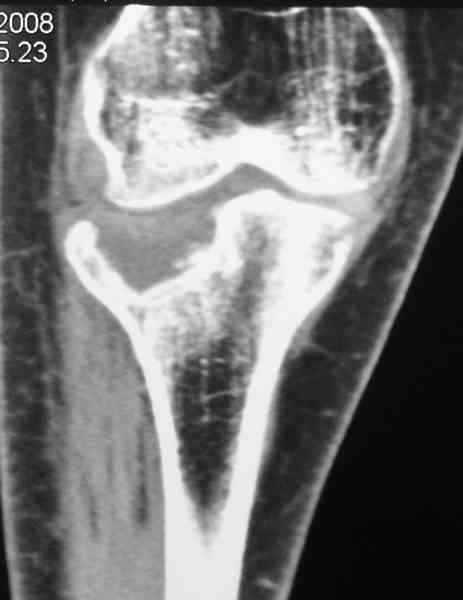

[Ortho] Застарелый перелом 41С3

Уважаемый Абдурашид. Если нет противопоказаний , то из оперативных

способов, я бы рекомендовал следующие: Полное замещение наружного

мыщелка аллотрансплантатом либо открытая репозиция с элевацией и

замещение дефекта ауто или аллокостью. В Ваших условиях , я бы

рекомендовал второй способ. Во-время элевации необходимо разъединить

фрагменты со стороны сустава ( надсечь скальпелем по линиям перелома,

а затем тонким остеотомом их разъединить. При помощи долота произвести

неполную остеотомию ( захватите не менее 1,5 - 2 см губчатой кости и

поднять фрагменты, визуально отрепонировать и фиксировать 2-3 спицами.

Дефект заместить костным ауто или аллотрансплантатом. Окончательная

стабилизация пластиной ( лучше с угловой стабильностью, либо АВФ -

позволит спокойно устранить угловую деформацию.